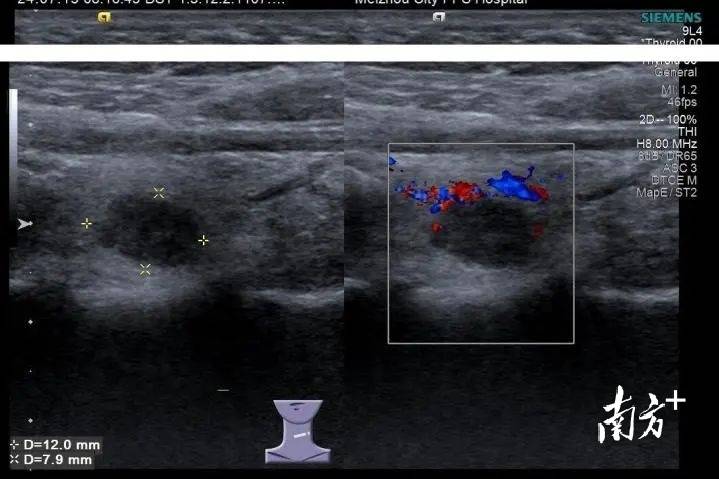

小罗是一名在校女大学生,家住在吉林省白城市,近期体检中发现甲状腺有个结节,彩超提示为C-TIRADS 4A类,存在恶性病变风险。看到检查报告时,小罗很害怕,“存在恶性病变风险”到底严不严重,要不要及时处理?

甲状腺结节是甲状腺内部的肿块,有良恶性之分,良性结节多为甲状腺瘤、结节性甲状腺肿、甲状腺囊肿等;恶性结节常见的是甲状腺癌。小罗体检中的4A类按照危险度属于四类,恶性程度的风险为5%—10%。

梅州市人民医院甲状腺外科副主任王悦冬在详细了解小罗病情后,建议小罗先行超声引导下甲状腺细针穿刺活检术,以明确结节性质,术后病理诊断为甲状腺乳头状癌,为恶性结节,有必要手术切除。